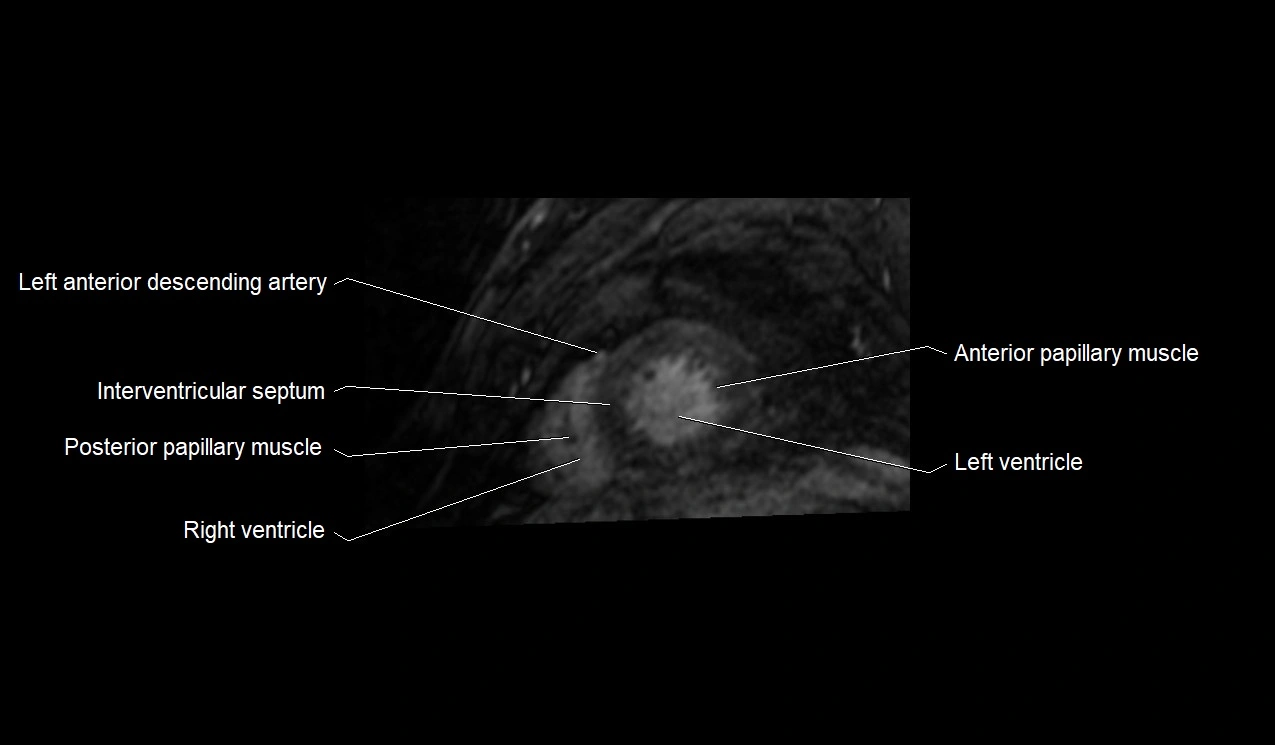

MRI image